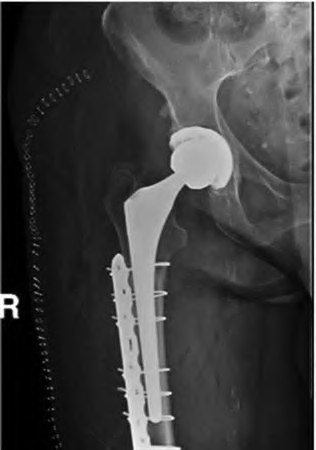

The radiograph demonstrates a periprosthetic femur fracture extending to the tip of the stem. The long spiral fracture is consistent with a loose implant. The bone stock is sufficient. Therefore, this fracture pattern would classify as a B2 using the Vancouver classification system. The Vancouver classification for periprosthetic femoral fractures is simple yet incorporates all the pertinent factors such a location, stem fixation, and bone stock. Type A is a trochanteric fracture- lesser or greater. These can be treated non-operatively usually and ORIF if symptomatic. Type B fractures are around or just below the stem and are subdivided into three types. Type B1 is a fracture with a well fixed stem.

The treatment is cable plating or allograft struts or a combination of the two. Type B2 is a fracture with a loose stem with good bone stock. The treatment is a cementless porous coated long stem atleast two diameter length past the

fracture site. Type B3 is a fracture with a loose stem and comminution. For younger patients, use cementless porous coated long stems with allograft struts. For older patients, consider a tumor prosthesis. Cement fixation is sometimes necessary Type C is a fracture well below the stem tip. These can be treated independently of the prosthesis.

Springer et al showed optimal outcomes with revision involving long extensively-coated femoral stems for Vancouver B fractures.